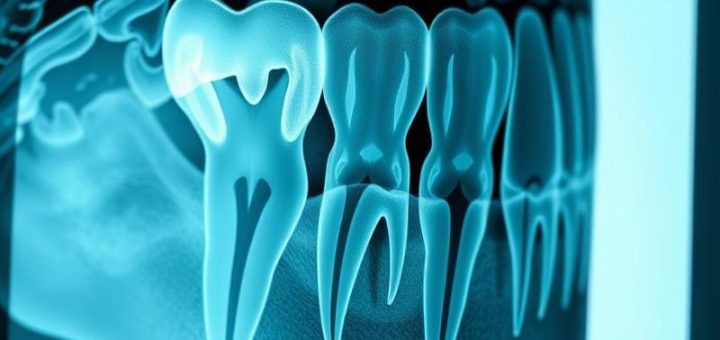

Czym jest rentgen stomatologiczny? To pytanie, które może zadawać sobie każdy pacjent odwiedzający gabinet dentystyczny. Rentgen stomatologiczny to niezwykle istotne narzędzie diagnostyczne, które wykorzystuje promieniowanie X do oceny stanu zębów oraz tkanek w jamie...